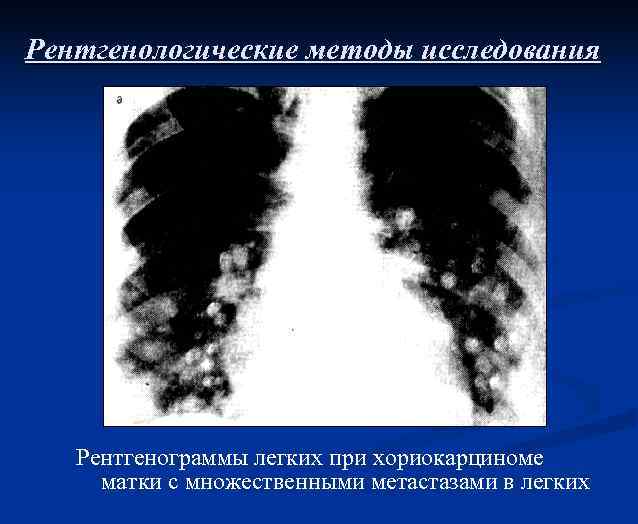

Рентгенологические методы исследования Солитарные метастазы хориокарциномы в правом легком

Рентгенологические методы исследования Рентгенограммы легких при хориокарциноме матки с множественными метастазами в легких

Рентгенограмма легких при хориокарциноме матки с множественными метастазами в легких до лечения

Рентгенограмма легких при хориокарциноме матки с множественными метастазами в легких после лечения